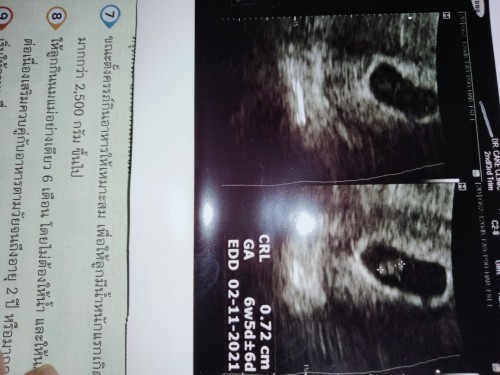

เมื่อวานนี้ วันที่ 18 มีนาคม 2564 เวลาประมาณ13.50 น. แม่มีมูกเลือดไหลออกมาปนกับตกขาว ด้วยความร้อนใจจึงรีบไปพบแพทย์ที่โรงพยาบาล คุณหมอได้ทำการ ตรวจช่องคลอด หมอบอกว่าปากมดลูกยังไม่เปิด แต่หมอจะพาไปอัลตร้าซาวด์ (ซึ่งเป็นการอัลตร้าซาวด์ทางช่องคลอด) ดูเพื่อความแน่ใจดีกว่า จะได้เห็นทารกด้วย พอไปอัลตร้าซาวด์ สิ่งที่ไม่อยากได้ยิน สิ่งที่ไม่อยากให้เกิดก็มาถึง คุณหมอบอกว่า "เหมือนน้องจะไม่อยู่แล้วนะครับคุณแม่" นาทีนั้นคืออึ้ง หมอพูดอะไร มันตัดไปเลย ได้แต่ถามตัวเองว่าทำไม หมอพูดแบบนั้นซ้ำๆแล้วหันจอมาให้แม่ดู คุณหมอบอกว่า "หมอไม่เห็นหัวใจของตัวอ่อน อายุครรภ์10week แล้ว แต่ตัวอ่อนมีขนาดเท่าอายุครรภ์ 7 week เอง " แล้วก็ยังชี้ให้แม่ดูต่อ "ตรงนี้คือส่วนหัวนะครับ ส่วนหัวใจจะอยู่ตรงนี้ แต่กมอไม่เห็น ซึ่งปกติแล้วเราจะมองเห็นจุดเล็กกระพริบๆๆอยู่ตรงนี้ สีของตัวอ่อนก็จางมาก โดยปกติสีจะต้องเข้มกว่านี้ และตัวอ่อนต้องลอยตัว หมอจะลองสั่นสะเทือนให้ดูนะ ถ้ามีการสั่นสะเทือน ตัวอ่อนจะลอยตัว แต่นี่เค้าอยู่นิ่งๆ ซึ่งค่อนค้างมั่นใจเลยแม่เค้าไม่อยู่แล้วจริงๆ" นาทีนั้นคือจุก พูดอะไรไม่ออก อยากจะปล่อยโฮก็ปล่อยไม่ได้ แต่แต่กลั้นไว้ และพูดคำเดียวว่า คะ หมอก็ยังพูดต่อว่า "ตอนนี้อายุครรภ์คุณแม่10 week อายุตัวอ่อน 7 week น้องน่าจะเสียมา3วีคแล้วนะครับคุณแม่ " แต่ในใจคือไม่เชื่อ ไม่จริง วันที่14 ยังไปตามนัดอยู่เลย คุณหมอซาวด์ผ่านหน้าท้องแล้วบอกว่า ได้ยินเสียงหัวใจไม่ชัด ซึ่งนั่นก็คงหมายความว่าน้องยังมีหัวใจ และยังเต้นอยู่ใช่มั๊ยคะ หลังจากที่แม่หาหมอวันที่14เสร็จ แม่ก็เซฟตัวเองตลอด นอนหลับพักผ่อนให้เพียงพอ ทำอะไรก็ระวังตลอด จนเมื่อวานนี้แม่เข้าห้องน้ำ พอเสร็จธุระแม่ก็เช็ดดูแล้วก็เห็นแบบนั้น โดยที่ไม่มีอาการใดๆเลย ไม่ปวดท้อง ไม่ปวดหลัง ไม่มีอาการผิดปกติใดๆ แต่ด้วยความร้อนใจจึงรีบไปโรงพยาบาล พออัลตร้าซาวด์เสร็จมารอพบคุณหมอ คุณหมอแนะนำให้ยุติการตั้งครรภ์ และจะนัดไปขูดมดลูกวันนี้ แต่แม่ยังทำใจไม่ได้ เลยขอหมอว่า แม่ขอเวลาอีก1อาทิตย์ได้ไหมคะ พูดออกมาทั้งน้ำตาและเสียงที่สั่นเครือ หมอก็บอกว่า ถ้าคุณแม่อยากให้โอกาสน้องอีก1อาทิตย์ ก็ไม่เป็นไร แต่จากการอัลตร้าซาวด์ในวันนี้คือค่อนข้าง100%แล้วนะครับ แต่ก็แล้วแต่คนไข้ครับ เดี๋ยวหมอจะให้หยุดงาน พักผ่อน 7วันนะ แต่ถ้าระหว่างนี้มีเลือดออก หรือปวดท้องรุนแรง ให้รีบมาหาหมอเลยนะครับ เพราะภาวะนี้คือ #ภาวะแท้งคุกคาม ซึ่งเด็กอาจจะมีหรือไม่มีชีวิต ซึ่งตอนนี้ 50/50 แต่เคสนี้น่าจะเกือบ100 เพราะหัวใจน้องไม่เต้นแล้ว แม่ก็ได้แต่นั่งฟังแล้วพูดว่าคัคุณหมอ แม่ได้แต่ขอให้มีปาฏิหาริย์เกิดขึ้นกับแม่ ขอให้หนูกลับมา ขอให้หัวใจลูกแม่กลับมาเต้นอีกครั้ง แม่ไม่อยากเสียหนูไปจริงๆ แม่เฝ้ารอหนูมาตลอด ครั้งแรกที่รู้ว่ามีแม่ดีใจมาก และตอนนี้ แม่ก็เสียใจมากเช่นกัน ขอให้แม่ๆทุกคนสังเกตุอาการของตนเองให้ดีนะคะ อย่าชะล่าใจเป็นอันขาด หากพบความผิดปกติให้รีบไปพบแพทย์เลยนะคะ ถึงแม้ว่าเราจะคิดว่าไม่เป็นอะไร แต่บางทีมันอาจจะสายเกินไปเหมือนเคสของแม่เอง แม่จะรอคอยการกลับมาอีกครั้ง แม่รักหนูมากนะลูก #เบบี๋10week 18/03/64